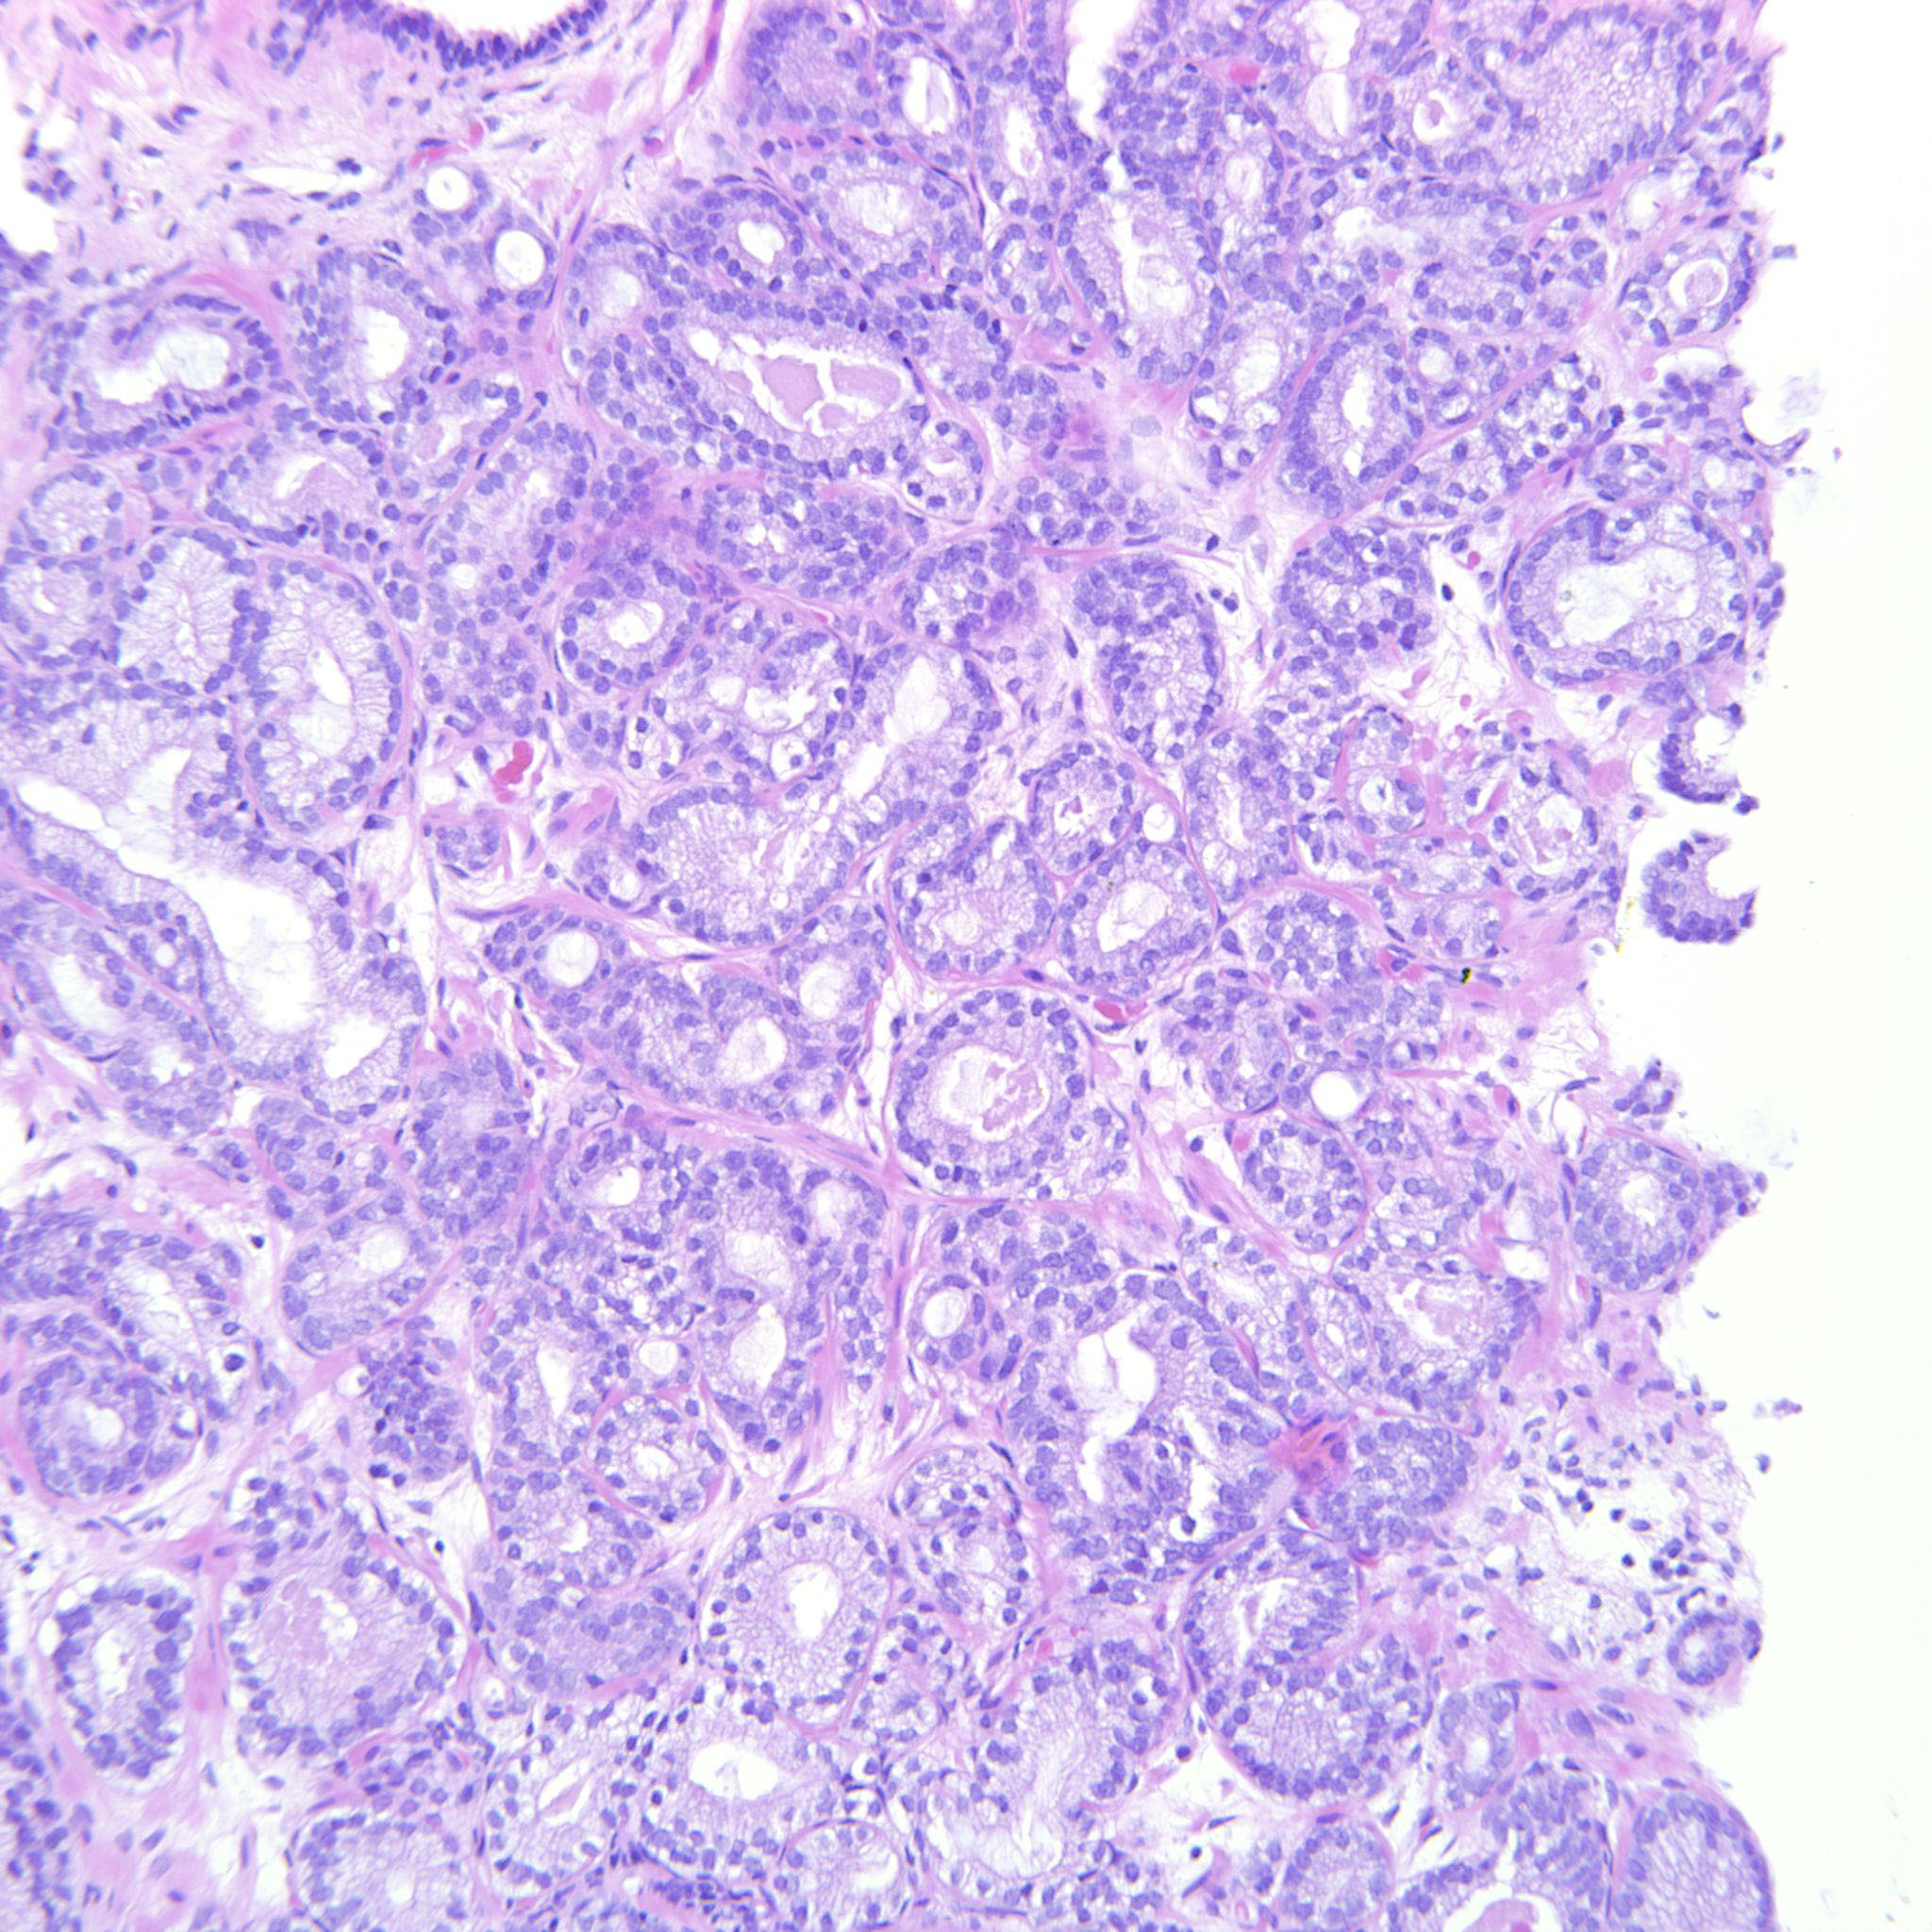

Consensus grade: GS 3+3=6 (ISUP 1)

Case description (by case creator):

3+3=6 with occasional seemingly poorly formed glands. These are however seen between well-formed glands and probably represent tangential cuts.

| Pathologist 2 | GS 3+4=7 (ISUP 2) | Typical |

Rare glands are fused |

| Pathologist 17 | GS 3+4=7 (ISUP 2) | Typical |

A couple of small, but convincing, cribriform glands present. |